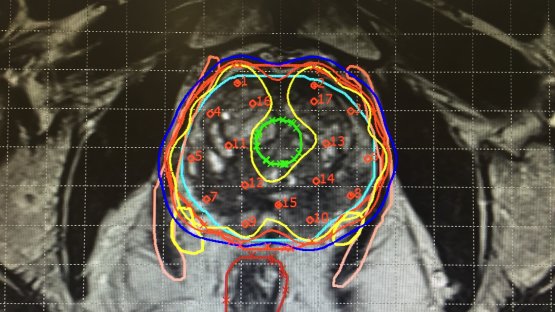

A New Vision for Cancer Treatment: Image Guided Brachytherapy